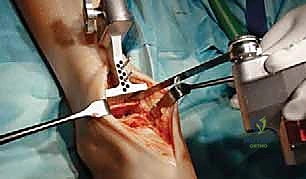

2. التخدير والشق الجراحي

تُجرى العملية عادة تحت التخدير العام أو التخدير النصفي (الشوكي). يقوم د. هطيف بعمل شق جراحي أمامي أو جانبي (حسب التقنية المستخدمة وحالة المريض) للوصول إلى مفصل الكاحل بعناية، مع الحفاظ على الأوتار والأعصاب والأوعية الدموية المحيطة.

3. إزالة الأسطح التالفة (تحضير العظام)

باستخدام أدوات جراحية دقيقة وموجهات خاصة، يتم إزالة الغضاريف التالفة وجزء رقيق جداً من العظام المريضة من نهايتي عظمة الظنبوب وعظمة الكاحل (Talus). يتم تشكيل العظام بدقة لتتطابق تماماً مع شكل أجزاء المفصل الصناعي.